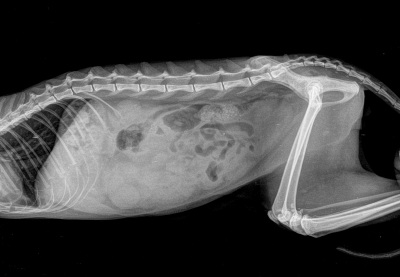

Опухоль живот кот

Опухоль живот кот 118 фото